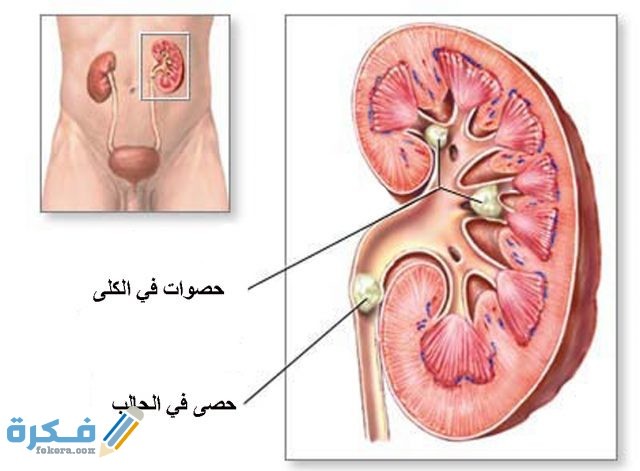

- حصوات الكلى عبارة عن مجموعة من الرواسب المكونة من الأملاح والمعادن المختلفة في الجسم .

- تتكون حصوات الكلى أثناء قيام الكلى بفصل الدم وتصفيته عن البول للتخلص من البول .

- تختلف أحجام حصوات الكلى حيث تكون احجامها مثل حبه السكر أو بحجم كرة التنس .

- أكثر أنواع حصوات الكلى انتشارا تلك التي يتراوح حجمها من 5 الى 10 ملم .

- تتكون حصوات الكلى في الكلى او في اى جزء من المسالك البولية ابتداء من الكلى وحتى المثانة .